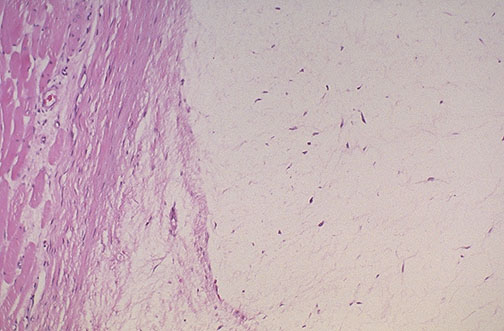

| This myxoma at the center and right is seen microscopically to be relatively acellular. Normal skeletal muscle and fascia appear at the left. The neoplasm is mostly composed of a "myxoid" material consisting of intercellular ground substances along with a few scattered spindle to stellate fibroblast-like cells. |